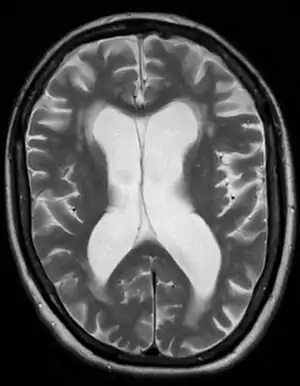

| Brain atrophy on MRI from vascular dementia | |